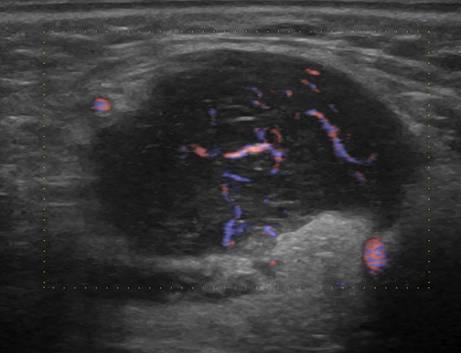

U tuyến nước bọt

» Thông tin: Nam giới – 63 tuổi.

» Lâm sàng: Khối vùng góc hàm.

# Lymphoma tuyến nước bọt dưới hàm.